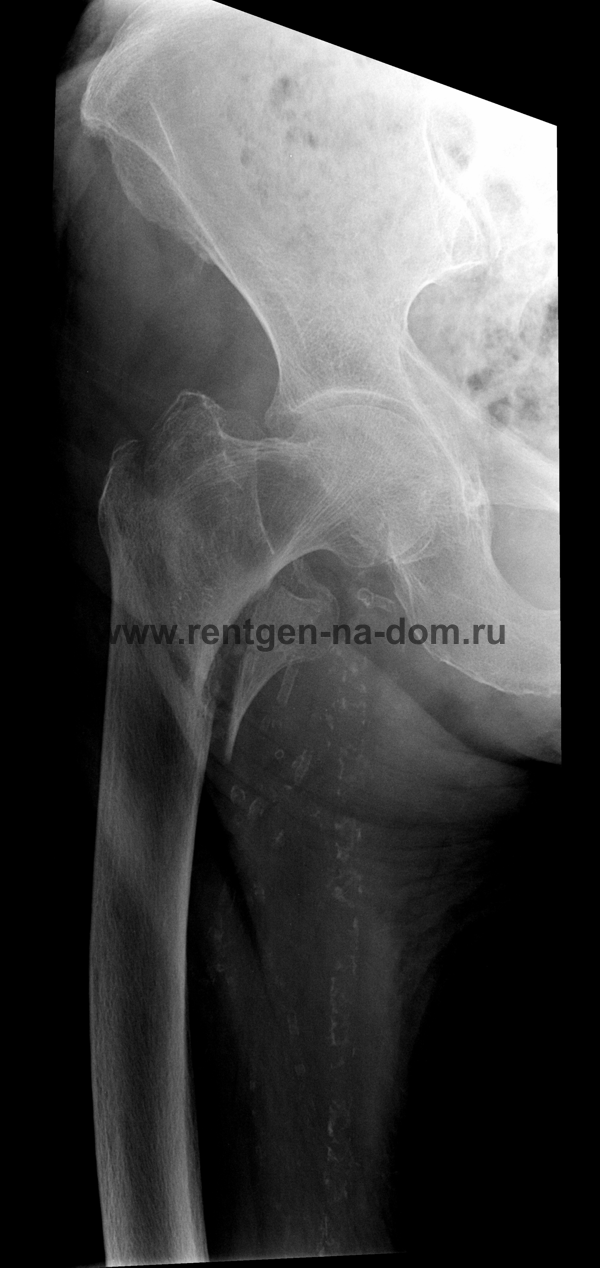

Перелом шейки бедренной кости.

Решающее значение в установлении диагноза перелома шейки бедра имеет рентгенография тазобедренного сустава. У пожилых пациентов приведенные выше симптомы могут проявляться нечетко, а такие заболевания как инсульт или невропатия, вообще, не позволят поставить правильный диагноз без рентгена. Где сделать рентген? Перелом шейки бедра всегда сопровождается сильной болью, поэтому любые лишние движения оборачиваются новыми мучениями, а сопутствующие заболевания внутренних органов усугубляют ситуацию! Решение есть - воспользоваться уникальной услугой – цифровой рентген на дому. К вам приедет врач рентгенолог-травматолог, который выполнит весь комплекс лечебно-диагностических мероприятий и подробно расскажет, что делать дальше.

Получение качественных рентгеновских снимков на дому предъявляет серьёзные требования к рентгеновской аппаратуре. Далеко не каждый переносной рентгенаппарат позволяет получать снимки необходимого качества, чтобы достоверно поставить диагноз. Используемый нами рентгенаппарат АРА 110/160 в комплексе с компьютерным радиографом позволяет получать цифровые рентгеновские снимки высокого качества у пациентов различной комплекции и является уникальной услугой в Санкт-Петербурге, предоставляемой на дому.